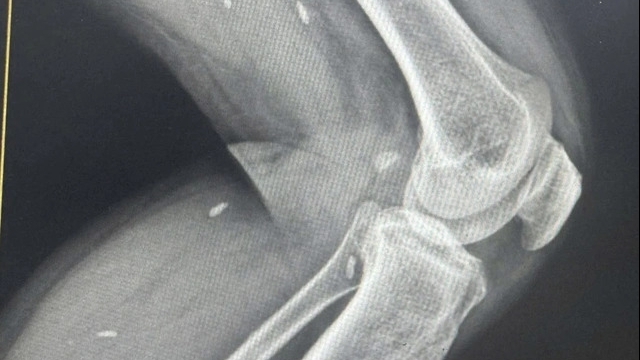

Nạn nhân là anh Chu Phi Hùng nhập viện trong tình trạng gãy 1/3 trên xương đùi trái do tai nạn lao động. Theo chẩn đoán của các bác sĩ, nạn nhân bị gãy liên mâu chuyển xương đùi trái, tiên lượng nặng, hội chẩn chuyển tuyến trên điều trị.